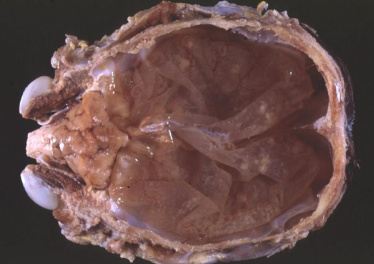

What is this condition in a cow?

Hydranencephaly